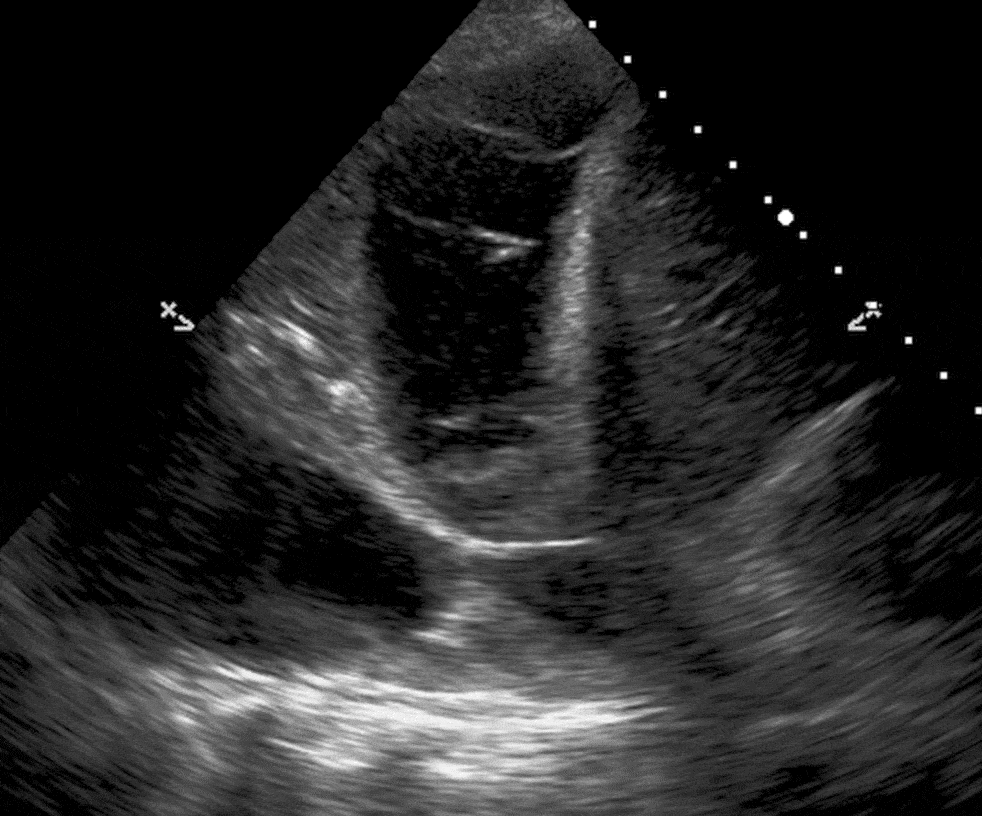

This cardiac view resembles a donut and croissant

What is the PSAX (parasternal short axis) view?

This chamber lies on top of the screen (near-field) on this cardiac view

What is the Right Ventricle?

This this apical 4 chamber view, the structures on the left side of the screen represent this side of the heart

What is the RIGHT side of the heart?

This view is the best to look for pericardial effusions

What is the subxiphoid (subcostal) view?

Left untreated, this finding can progress to this life-threatening clinical diagnosis which presents with hypotension/shock.

(You must name BOTH the current POCUS finding and the diagnosis we worry it might progress into)

What is a pericardial effusion (finding) causing a cardiac tamponade (clinical diagnosis)?